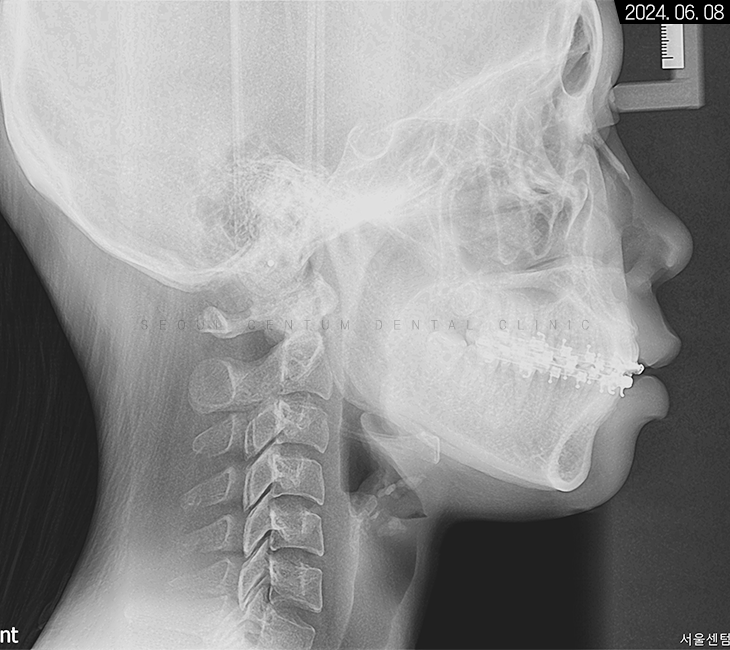

치아 교정에 들어가기 전에는

구강의 전체적인

해부학 구조 상황을 살펴보기 위해

파노라마 엑스레이 등의

사진 촬영이 반드시 필요합니다.

세팔로 측면 사진을 보면

확실히 수평피개 상태가 눈에 띄고

코끝부터 턱 끝까지 심미선을 그었을 때

입술이 과하게 넘어간 것을 볼 수 있었는데요.

입이 튀어나와서

아래턱이 들어간 양상도 보이지만

치아 전돌을 해소하면

아래턱이 자연스럽게 전상방으로 올라와서

구조적으로 정상 범주에 돌아오게 됩니다.

치조골 상태는 양호해서

치근 이동에 무리가 없을 것으로 예상됐고요.